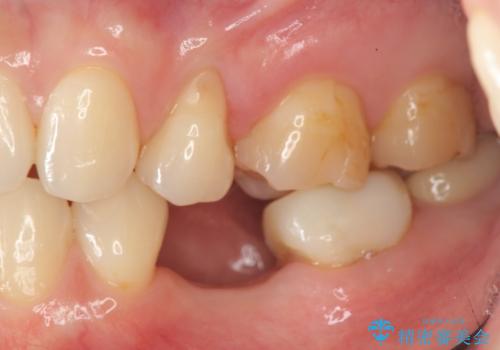

- 残していた乳歯がぐらつき始め、抜去ののちのインプラント治療を希望され来院されました。

生まれつき永久歯の欠損がある場合、乳歯が大人になっても残っている場合があります。

残念ながらぐらつきが大きくなり、残すことが難しくなり抜去したのちインプラントを用いて咬合機能の回復をしっかりと行いました。